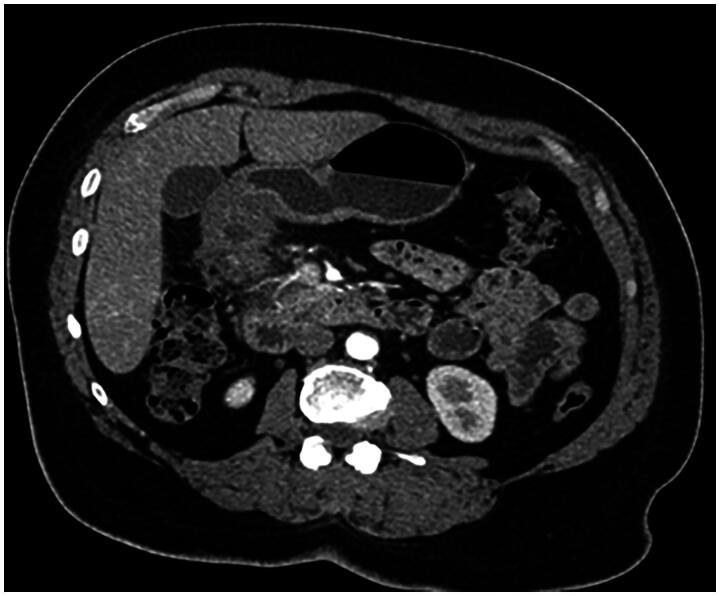

Duodenal bulb adenocarcinoma is a rare malignancy of the gastrointestinal tract. This cancer often presents with an insidious onset, making it challenging to diagnose early. A noteworthy case-study involved a 56 year-old-woman complaining from epigastric transfixing pain, jaundice, and overall health decline. The initial diagnosis suspected was a pancreatic tumor. An abdominal CT scan however showed no abnormality in the pancreas but revealed on the other hand an irregular, non-stenosing, heterogeneous fibrous thickening of the lower aspect of the duodenal bulb. An EGD showed a congested infiltrated area in the post-bulbar region, and Pathological exam confirmed the diagnosis of a primary adenocarcinoma of the duodenal bulb. The purpose of this article is to present the case of a primary adenocarcinoma of duodenal bulb mimicking a pancreatic tumor: a rare presentation of a rare tumor itself and to present points differentiating these two neoplasms. Diagnosis relies on a comprehensive assessment involving clinical, radiological, endoscopic, and histologic features. Integration of advanced imaging modalities, such as CT/MRI, coupled with upper gastrointestinal endoscopy, is crucial for accurate evaluation.